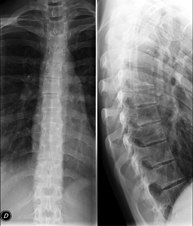

- Thoracic spine X-ray

This technique uses X-ray rendered imaging to examine the thoracic spine. Indicated for: trauma, back pain.

- Spinal teleradiology

This technique uses X-ray rendered imaging to examine the entire spinal column, especially assessing the presence of scoliosis and pelvic dysmetria.